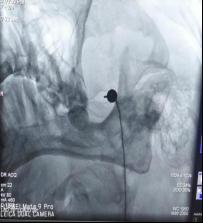

什么是三叉神经射频术(2015年开始开展技术)

在影像学精确引导下(如图2),将射频电极穿刺到病变的三叉神经分支处,通过温控加热,选择性地破坏痛觉纤维,从而阻断疼痛信号的传导,达到有效止痛的目的,不影响面部触觉、温度觉及出现面瘫现象。